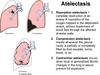

Atelectasis is the collapse of part or all of a lung due to loss of _____ ___. It may be caused by bronchial obstruction, loss of blood supply, or inability of a lung to ______. Airay obstruction leads to atelectasis within minutes or hours, depending on the ____ of obstruction.

alveolar air

expand

degree

Loss of blood supply results in atelectasis within ___ hrs. Positional atelectasis occurs in the ______ (down) lung within a few minutes during anesthesia but it is reversible. Obstruction of the ____ ____ lung lobe is common in cats with asthma due to acumulation of bronchical ______. Clinical signs are related to underlying etiology and my include pain, cough, tachypenia, dyspnea, or hemoptysis.

DDFs for lung collapse?

24

dependent

right middle

exudate

Pneumonia

Pulmonary contusion/hemorrage